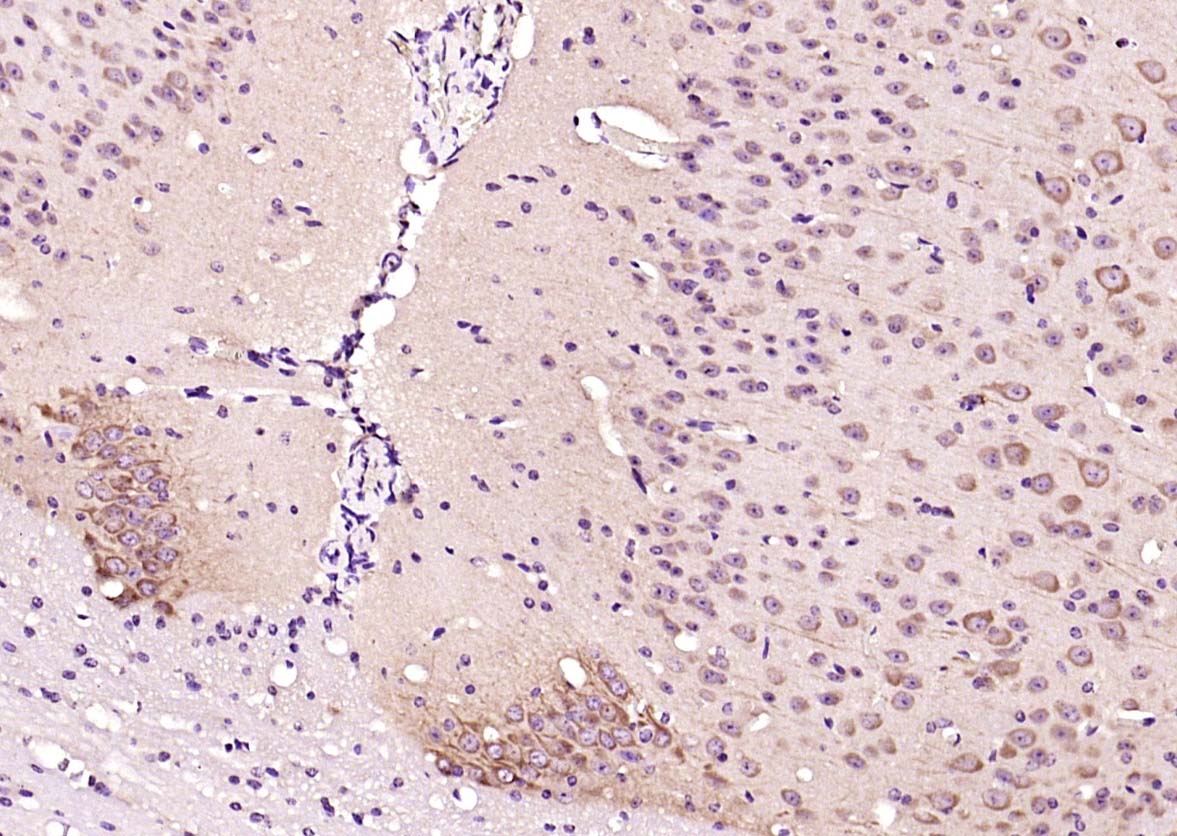

Paraformaldehyde-fixed, paraffin embedded (mouse brain); Antigen retrieval by boiling in sodium citrate buffer (pH6.0) for 15min; Block endogenous peroxidase by 3% hydrogen peroxide for 20 minutes; Blocking buffer (normal goat serum) at 37°C for 30min; Antibody incubation with (GDNF) Polyclonal Antibody, Unconjugated (bs-6949R Factor B) at 1:200 overnight at 4°C, followed by operating according to SP Kit(Rabbit) (sp-0023) instructionsand DAB staining.